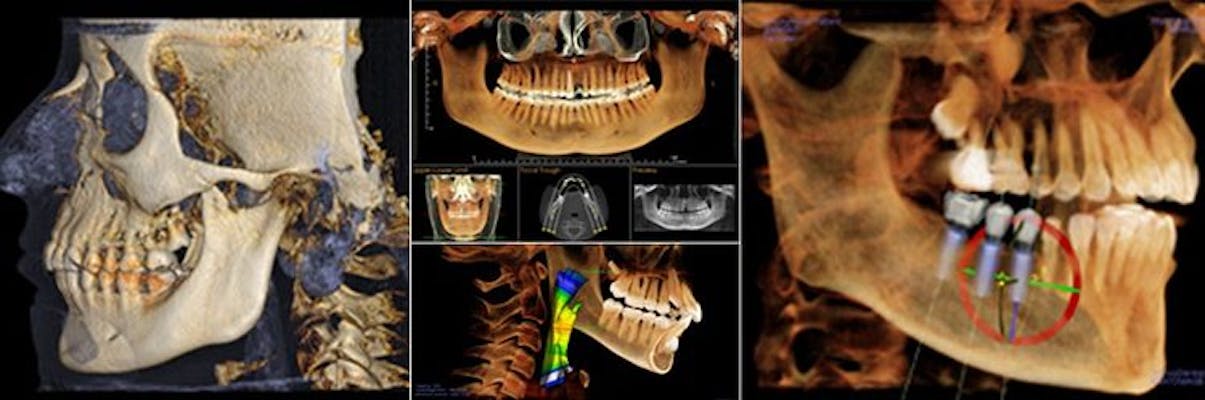

Cone Beam Volumetric Topography (CBVT, sometimes referred to as CBCT) allows us to quickly and safely diagnose many conditions related to your oral health. It also allows us to accurately image vital anatomical structures, making implant placement and surgical procedures safer.

ORTHOPHOS XG 3D. The most popular x-ray unit in the world. Now with 3D. With a perfectly designed 3D cylinder volume of 8 cm in diameter and 8 cm in height and a standard resolution of 160 µm, ORTHOPHOS XG 3D is precisely tailored to the everyday routines of private practices: it can capture the patient's whole jaw in a single span.